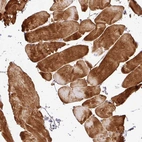

Immunohistochemical staining of human skeletal muscle shows strong cytoplasmic positivity in myocytes.